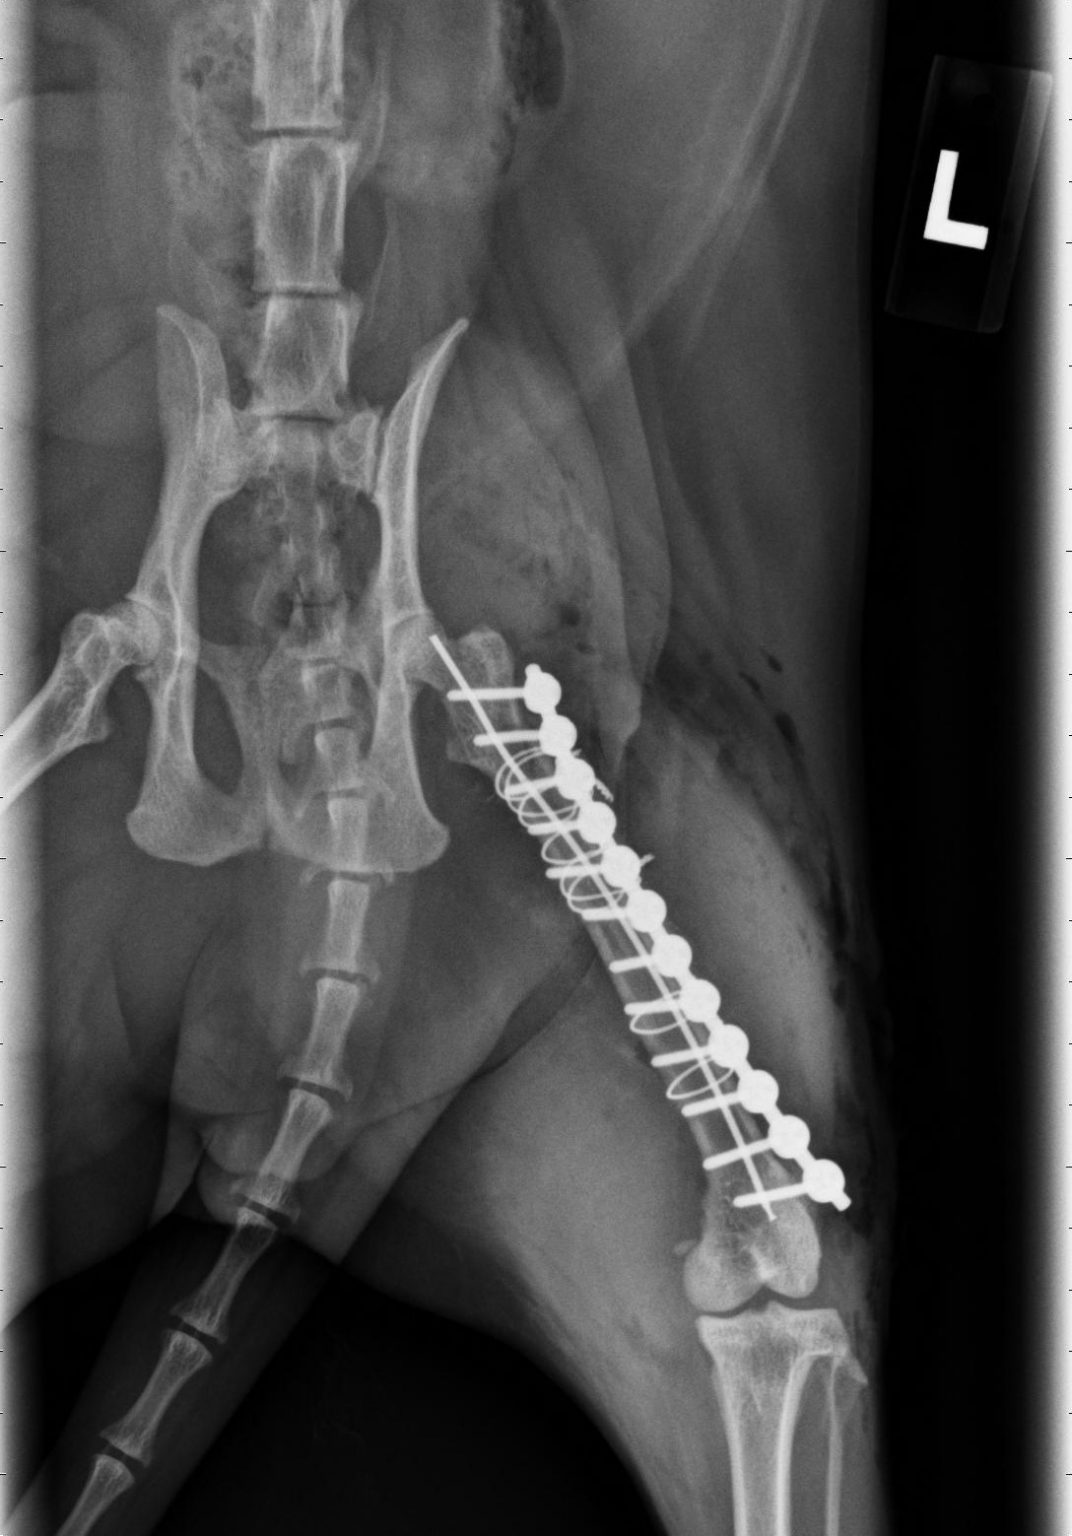

(PDF) Management Femoral Fracture in Cats using Intramedullary Pin and

20180316 【Fracture of femur、tibia and fibula】A cat , fixed with PRCLS Cat Broken Femur Recovery Time fracture repair is usually effective and carries a good to excellent prognosis in most cases, with cats resuming normal activity levels within. practical relevance:the femur is the most commonly fractured bone in cats. fractures of the femur (thigh bone) are some of the most common fractures seen in cats. Hang in there, baby—it can take anywhere from. Cat Broken Femur Recovery Time.

Cat lateral radiography showing oblique overriding femoral diaphyseal Cat Broken Femur Recovery Time in cats, the bones most likely to break are the femur (thigh bone), pelvis, jaw, and tail. what does recovery look like when your cat? practical relevance:the femur is the most commonly fractured bone in cats. while it can take eight to 12 weeks generally for full bone healing, recovery from pelvic fractures may take less. Cat Broken Femur Recovery Time.